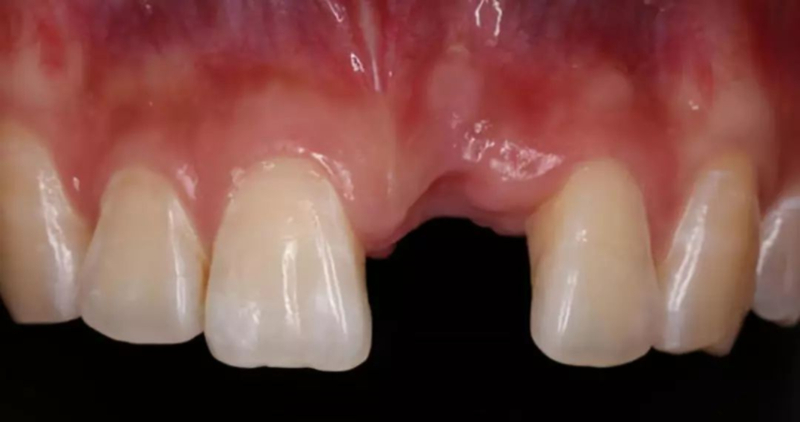

*前牙美學區(qū)種植,病人為正畸治療后,對美學要求高

*早期種植病例,頰側(cè)組織凹陷,肉眼可見骨缺損,需要種植同期GBR